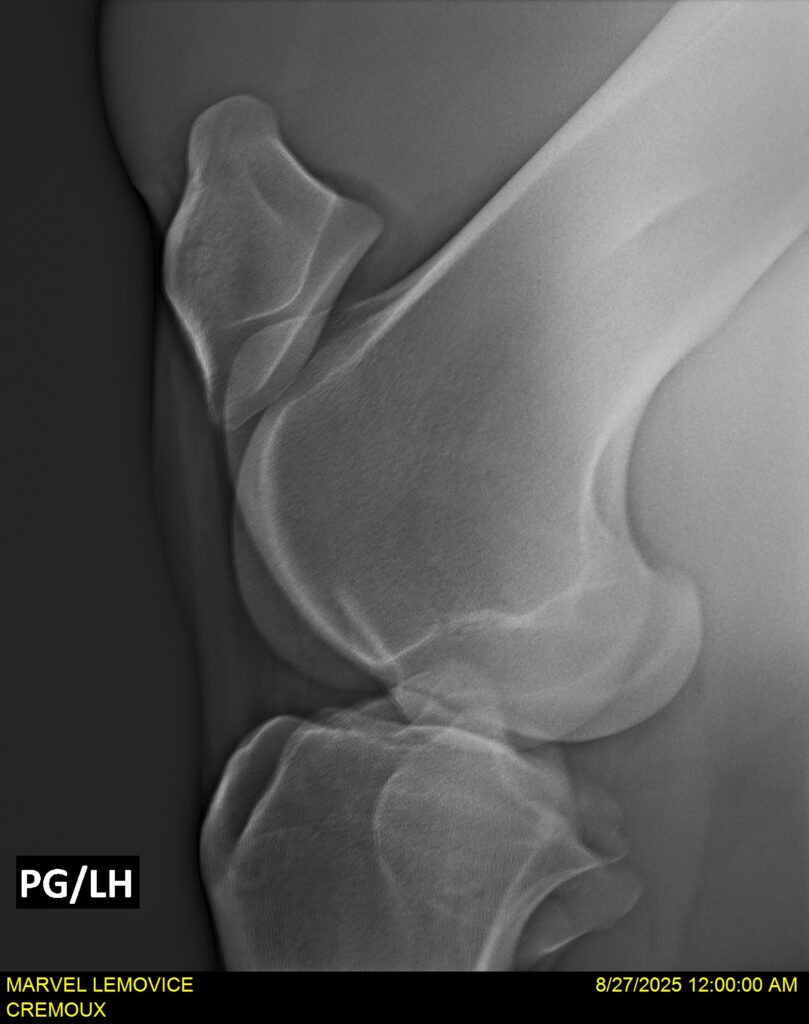

MARVEL LEMOVICE, hongre, Selle Français prend 4 ans en 2026. POPSTAR LOZONAIS x ROSIRE sur une excellente souche maternelle de l’élevage PLATIERE. Débourré aux trois allures et mise en route à l’obstacle. Super modèle avec du cadre et de la force, cheval respectueux avec des moyens. Très agréable au quotidien. Transport OK, maréchalerie OK, santé RAS, Bilan 20 clichés radios + clinique OK.

RADIOS ET CLINIQUE